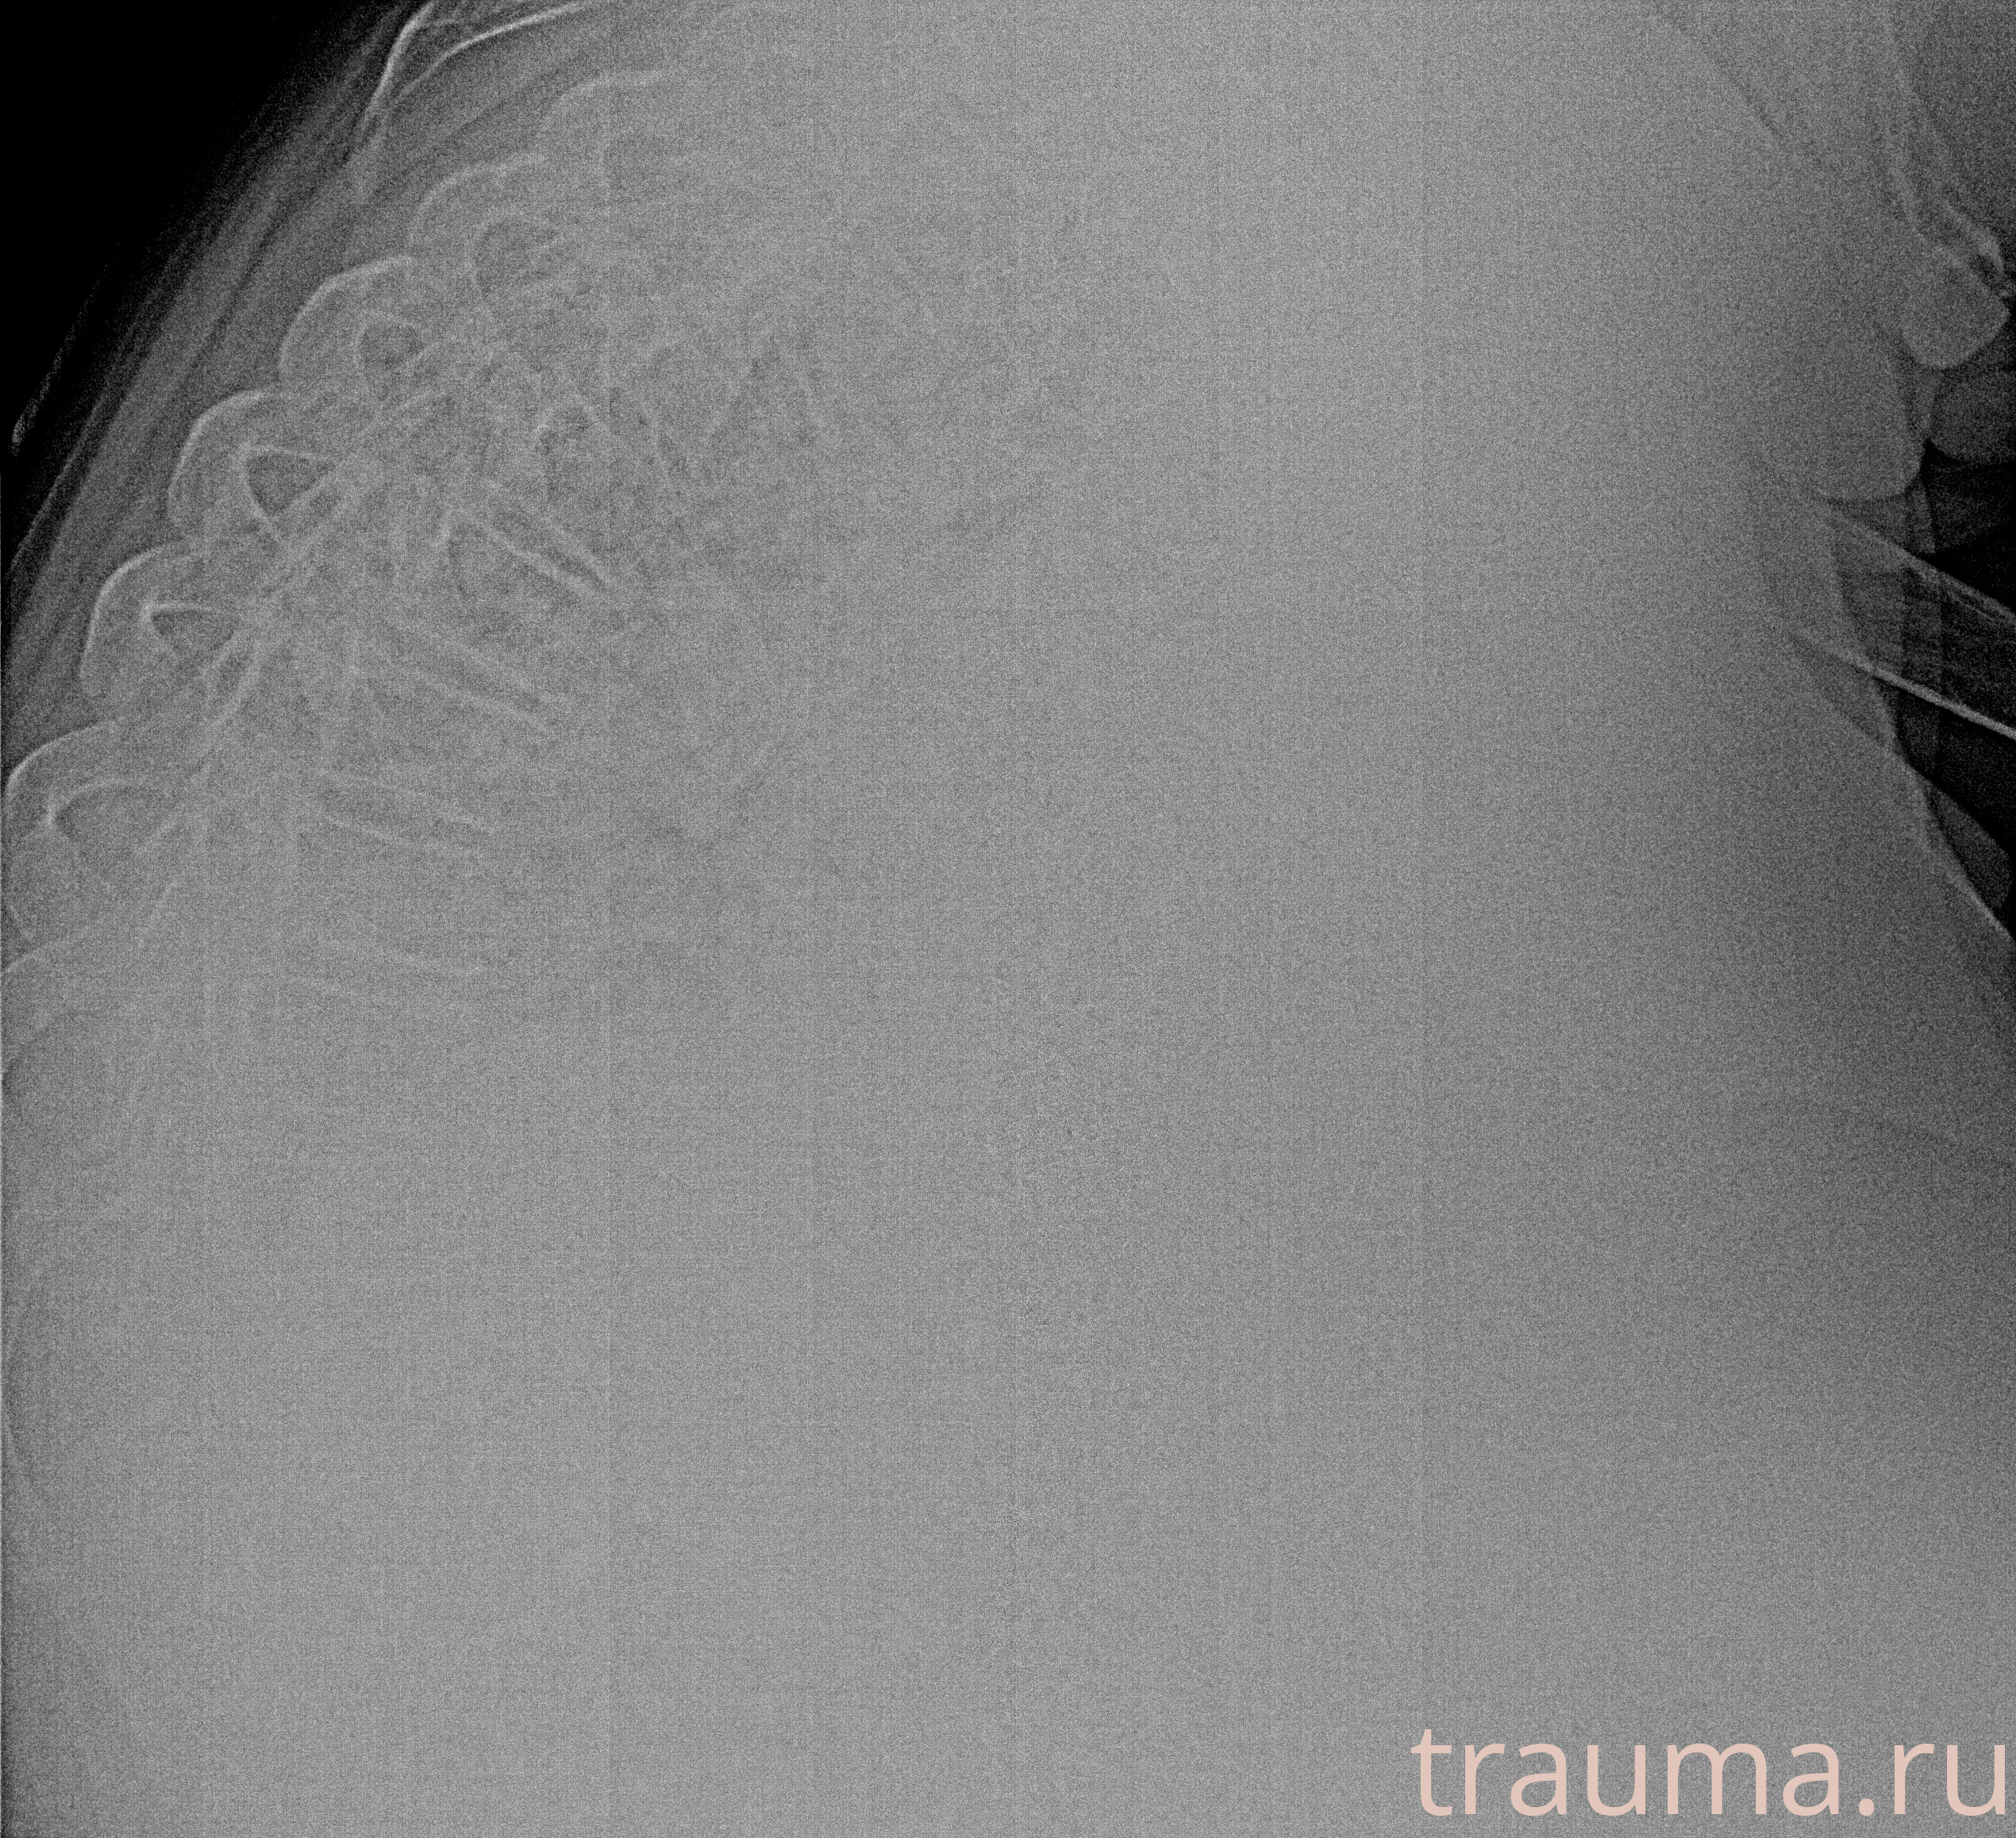

Рентгенограммы

Рентген на дому: по вашему адресу приезжает врач-рентгенолог, травматолог-ортопед с мобильным рентгеновским аппаратом, проводит диагностику травмы или заболевания, делает необходимые рентгенограммы, дает рекомендации по дальнейшему лечению. Получить качественные снимки в домашних условиях возможно благодаря уникальной методике, разработанной МосРентген Центром для института  Склифосовского